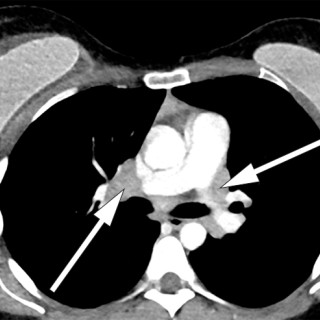

En yngre mann ble innlagt med venstresidige respirasjonsavhengige brystsmerter. Han hadde lett nedsatt allmenntilstand og feber. Det skulle bli et lengre sykehusopphold, der man diagnostiserte en uvanlig årsak til lungeaffeksjon. En tidligere frisk mann i slutten av tenårene ble via legevakt innlagt i sykehus etter ett døgn med venstresidige, respirasjonsavhengige smerter. Ved innkomst hadde han temperatur 37,6 °C, puls 117 slag/min, blodtrykk 104/57 mm Hg, respirasjonsfrekvens 24/min og perifer O2-metning på 94 % uten ekstra oksygentilførsel, og normale forhold ved klinisk undersøkelse...